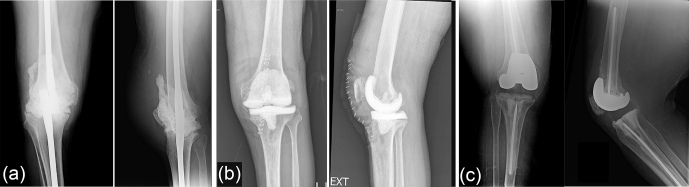

Introduction: Two-stage revision with an antibiotic spacer is the gold-standard treatment of prosthetic joint infection (PJI) for total knee arthroplasty (TKA). Multiple spacer designs exist, including static, articulated, and prosthetic low-friction (PALF) spacers. However, current literature is limited on variant superiority for infection eradication. This study aimed to compare outcomes of two-stage exchange for TKA PJI between patients with static cement, articulated cement, and PALF spacers. Methods: This retrospective study included 93 patients who underwent two-stage revision for PJI following primary TKA and received a static ( n = 17 ), articulating ( n = 54 ), or low-friction ( n = 22 ) spacer. The primary outcome was failure at 2 years, defined as spacer retention, reoperation, or death. Secondary outcomes included reimplantation and discontinued antibiotics by 1 year, time to failure, duration of hospital stay, functional measures, and adverse events. Outcomes were compared between groups using hypothesis testing for continuous or categorical measures. Results: At 2 years, no significant difference in failure was seen for static (58.82 %), articulating (35.19 %), and PALF (22.73 %) spacers ( p = 0.064 ). Articulating spacers demonstrated greater range of motion than static spacers at the final follow-up ( p = 0.0 3). Static spacers were associated with a higher adverse-event frequency ( p = 0.03 ). No other significant differences in outcomes were observed (all p > 0.05 ). Conclusions: The three spacer variants demonstrated similar failure rates for two-stage revision of TKA PJI at 2 years. Static spacers may lead to adverse events more frequently compared to other designs, and a longer interstage duration for prosthetic spacers may reflect greater functionality.